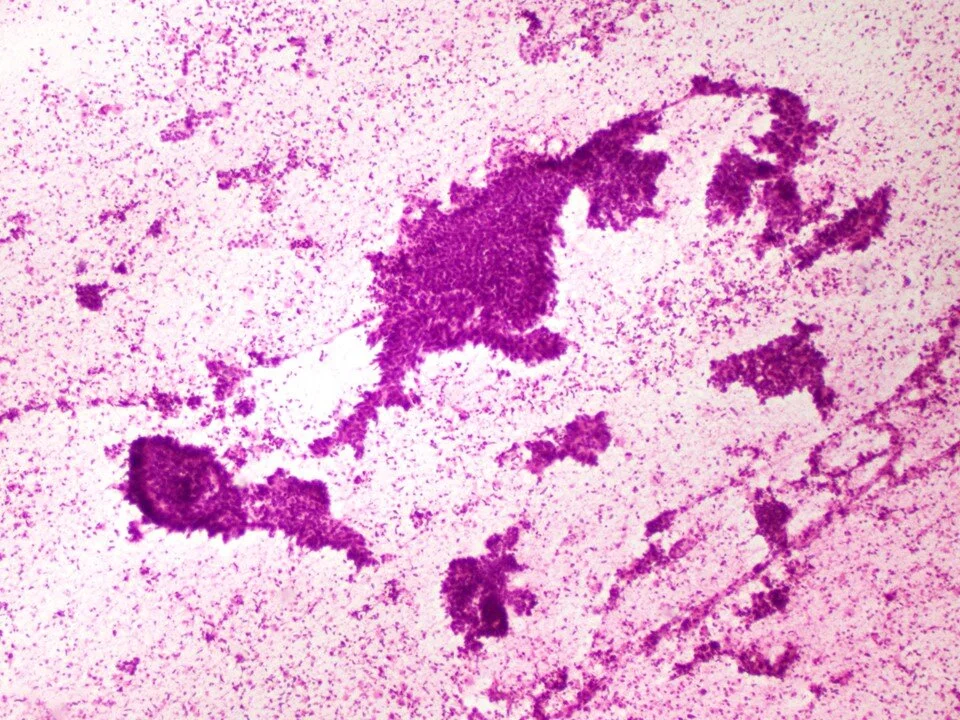

Pneumocystis jirovecii